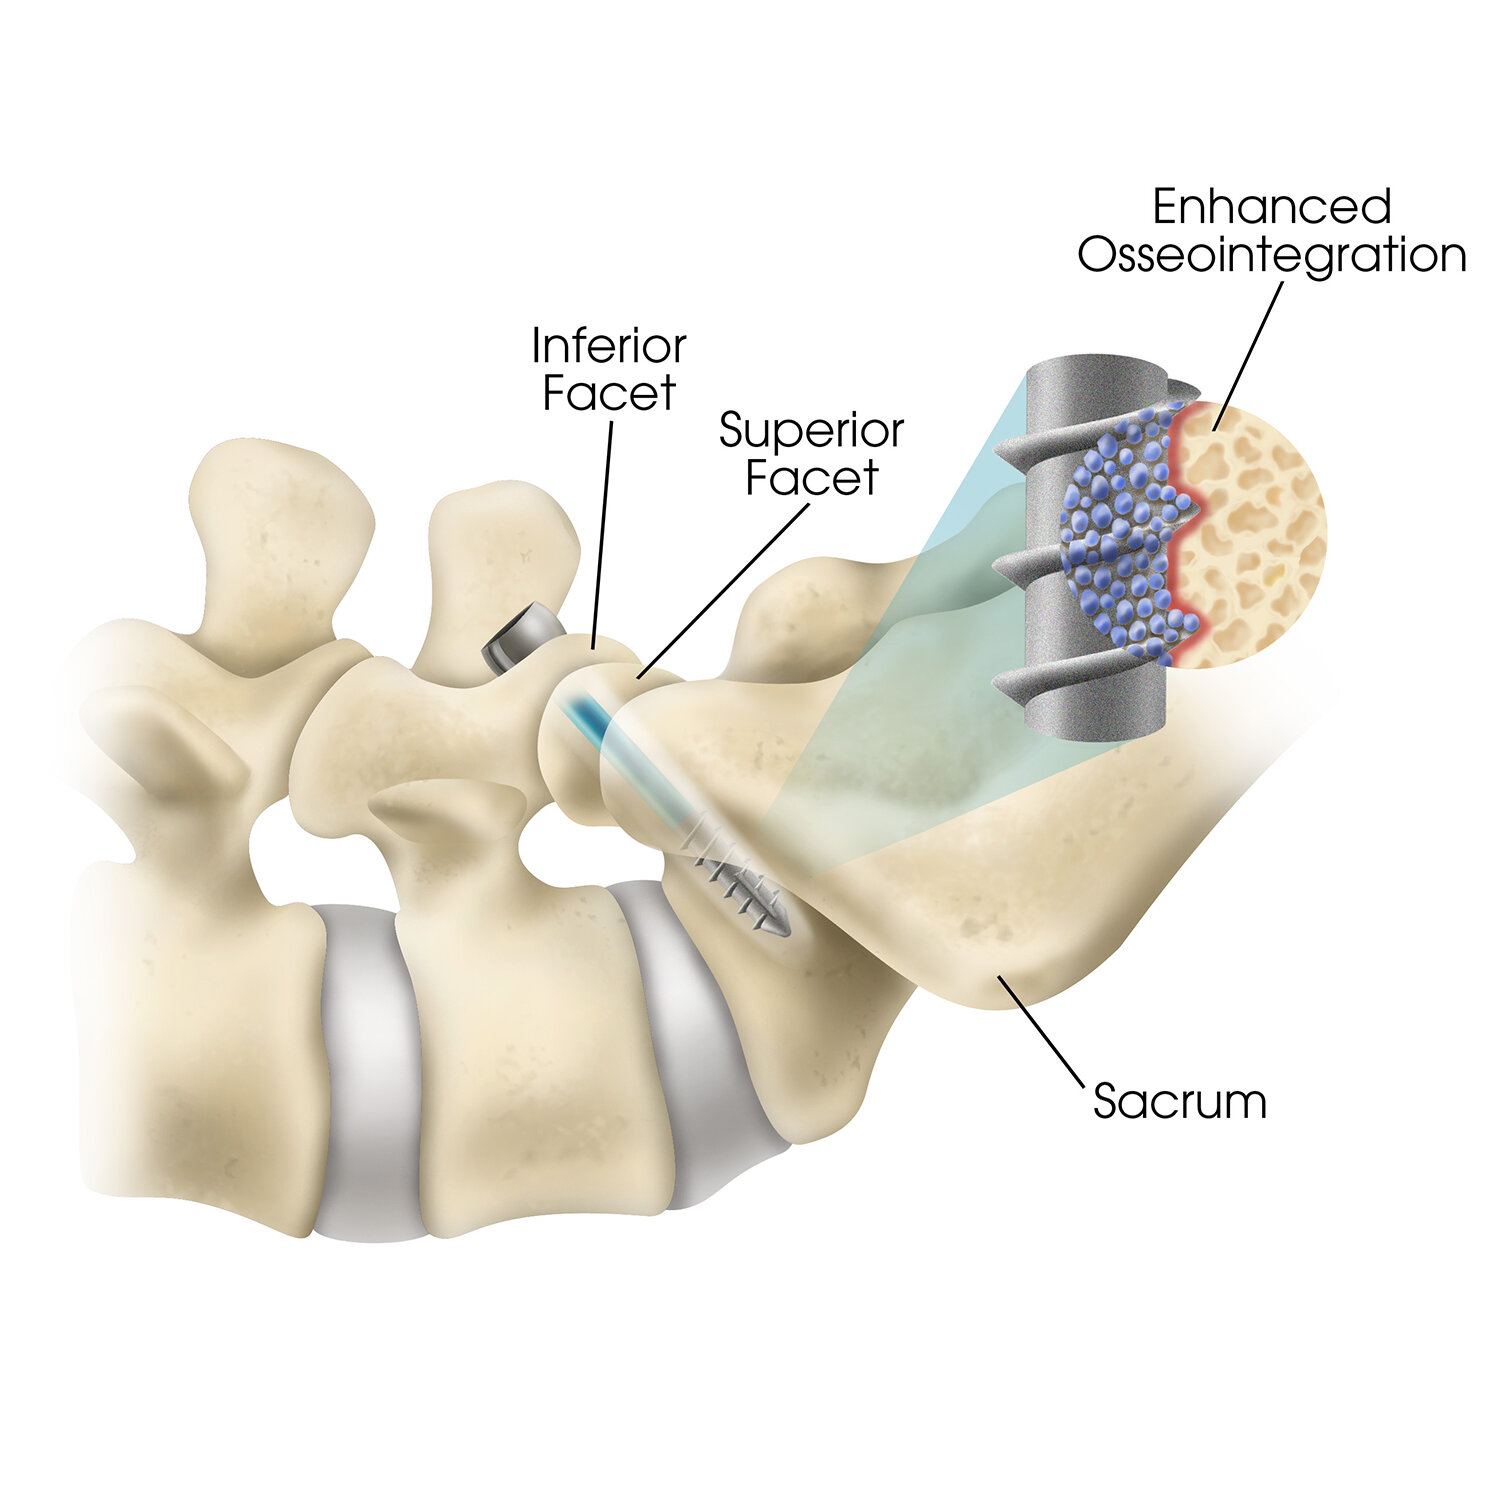

![Facet fixation]()

Facet fixation